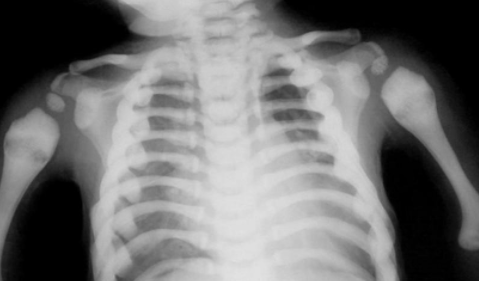

Imagerie

- Epaississement Osseux

- Sclérose diffuse

- Elargissmeent et bandes aux métaphyses